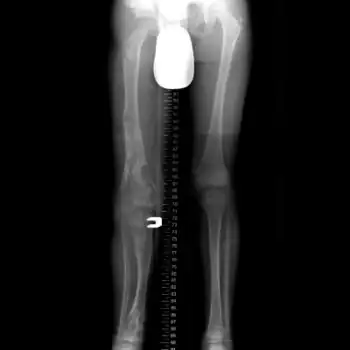

X-ray legs: Ollier disease